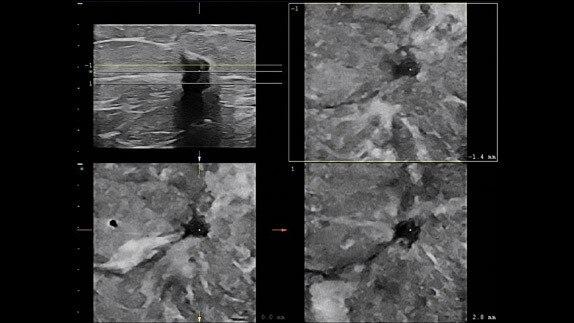

Lesion correlation of MRI and ultrasound using Multi-modality Query Retrieve and the ML6-15 transducer